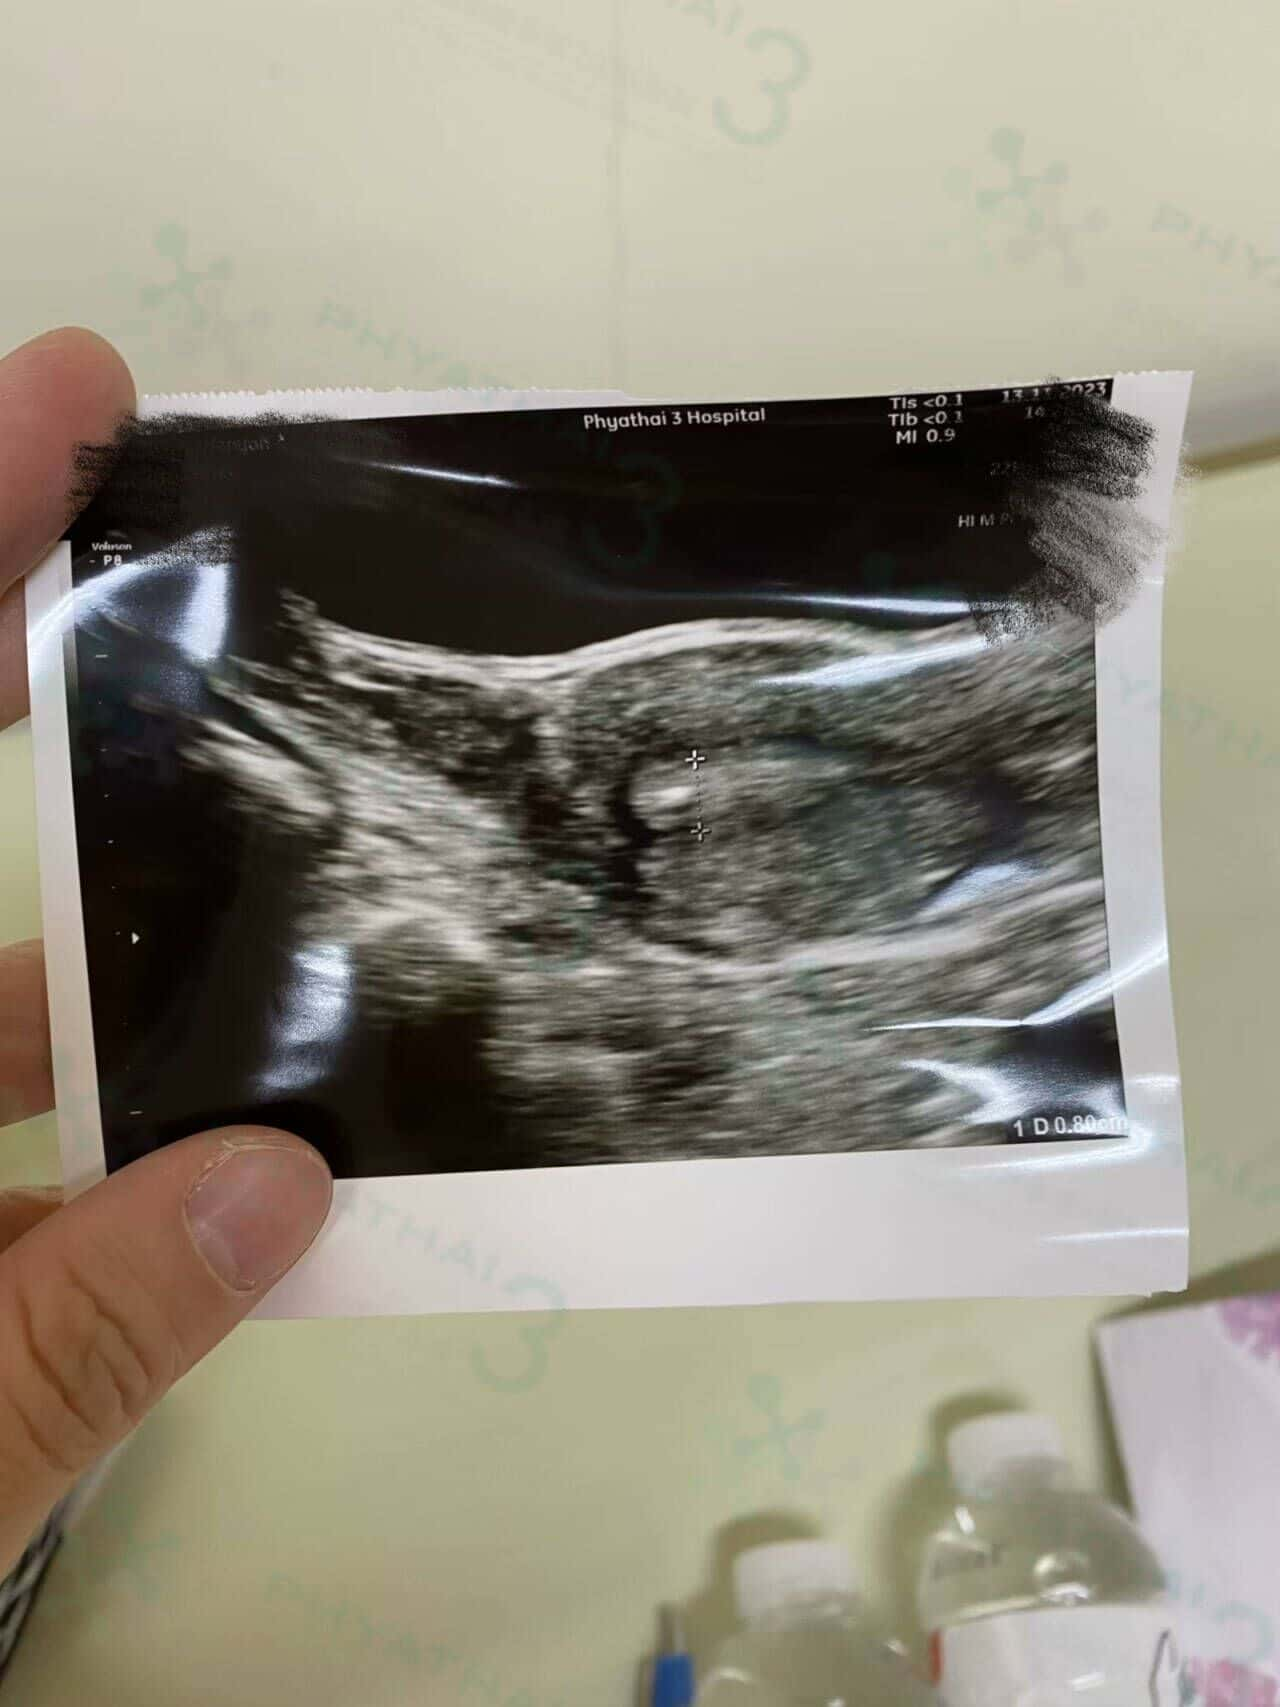

那天,从胚胎变成了一个小帅哥的宝宝

那天,从胚胎变成了一个小帅哥的宝宝,今天宝宝开始长大并看到他的器官。时间过得很快。来自刚刚促排,取卵并将移植胚胎。今天患者已怀孕3个多月了。宝宝发育得很好。做检查的时候不仅妈咪兴奋,但宝宝也很兴奋,因为他的心跳得很快。患者也说做试管是一个奇迹。从卵到胚胎,再从胚胎到今天的小帅哥。 祝之后小帅哥一直发育良好,下次妈咪再过来检查看你的发育噢。